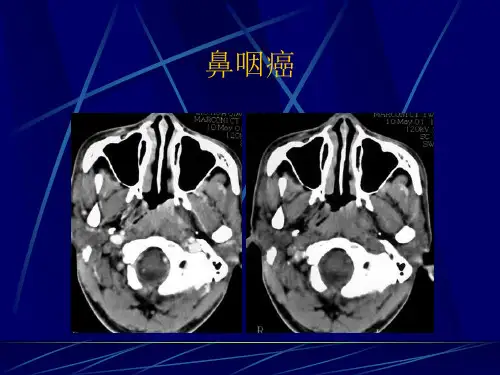

鼻咽癌的新型影像学检查与诊断近年来,鼻咽癌的发病率逐年攀升,给人们的健康带来了巨大的威胁。

因此,对于鼻咽癌的早期发现和准确诊断变得尤为重要。

随着医学影像学技术的不断发展,新型的影像学检查方法在鼻咽癌的早期筛查和诊断方面发挥着重要作用。

本文将介绍几种新型的影像学检查方法,并探讨其在鼻咽癌诊断中的应用。

一、MRI(磁共振成像)MRI是一种非侵入性的影像学检查方法,具有优异的软组织对比度和解剖性分辨力。

对于鼻咽癌的早期诊断和病程监测非常有价值。

通过对鼻咽部进行高清晰度的影像学观察,可以观察到肿瘤的大小、位置以及周围组织的受累情况。

此外,MRI还可以对淋巴结的转移情况进行评估,为治疗方案的选择提供依据。